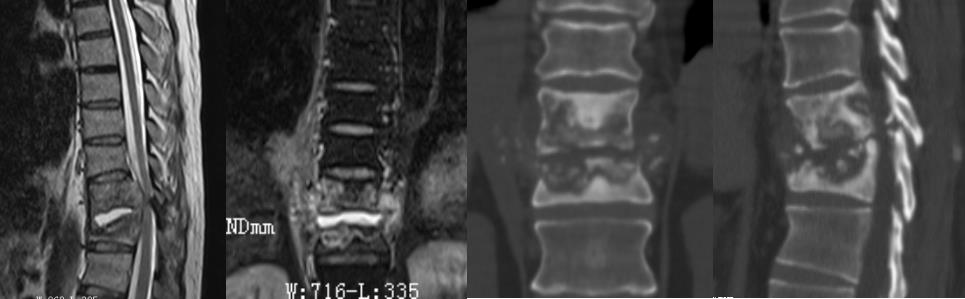

病例 胸10.11椎体结核并双下肢不全瘫,后路胸椎结核病灶清除植骨内固定术。

患者51岁,男性,胸10.11椎体结核

患者术前双下肢麻木、乏力,下肢肌力2-3级。